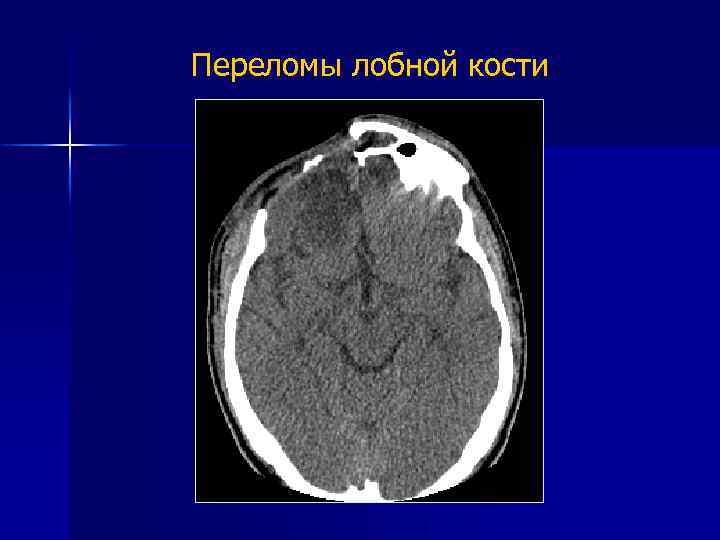

Переломы лобной кости